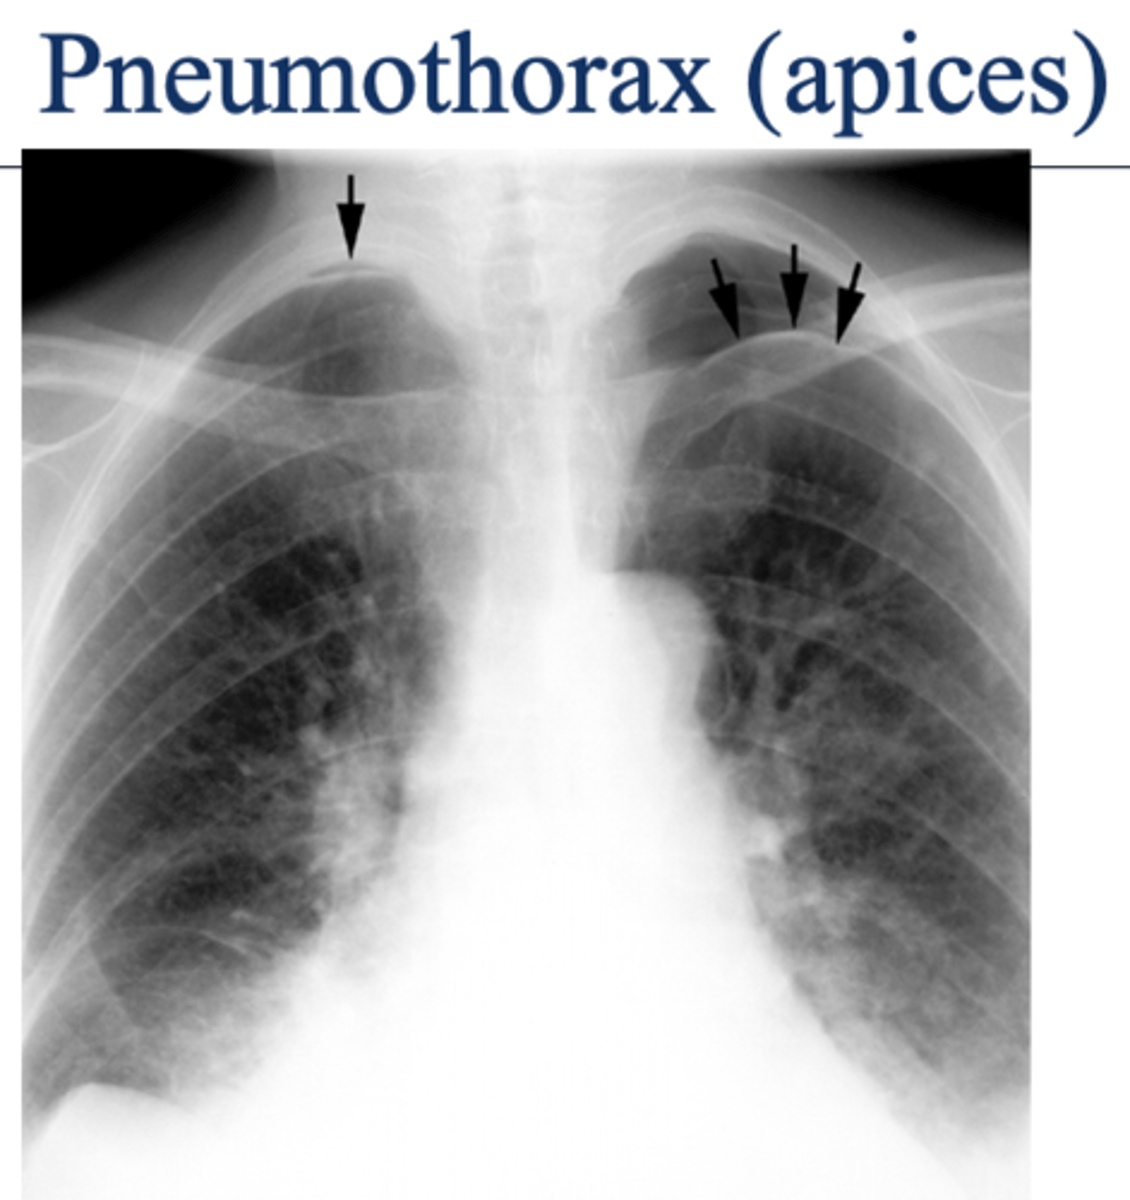

oAir in the pleural space (pneumothorax) is usually seen in the apices if the patient is upright.

Seen as an area of no vascularity and a thin white line representing the visceral pleura

**air has no density (so air will show up as darker)

L sided moderate pneumothorax

-mediastinal shift

-less density (darker)

-sharp line if non-tension pneumothorax

Pneumothorax (caused by stabbing)

visceral pleural line in the left chest (white arrows).

horizontal line along the base of the left hemithorax, which represents an air-fluid level (black arrows), showing that the patient has a hemopneumothorax.